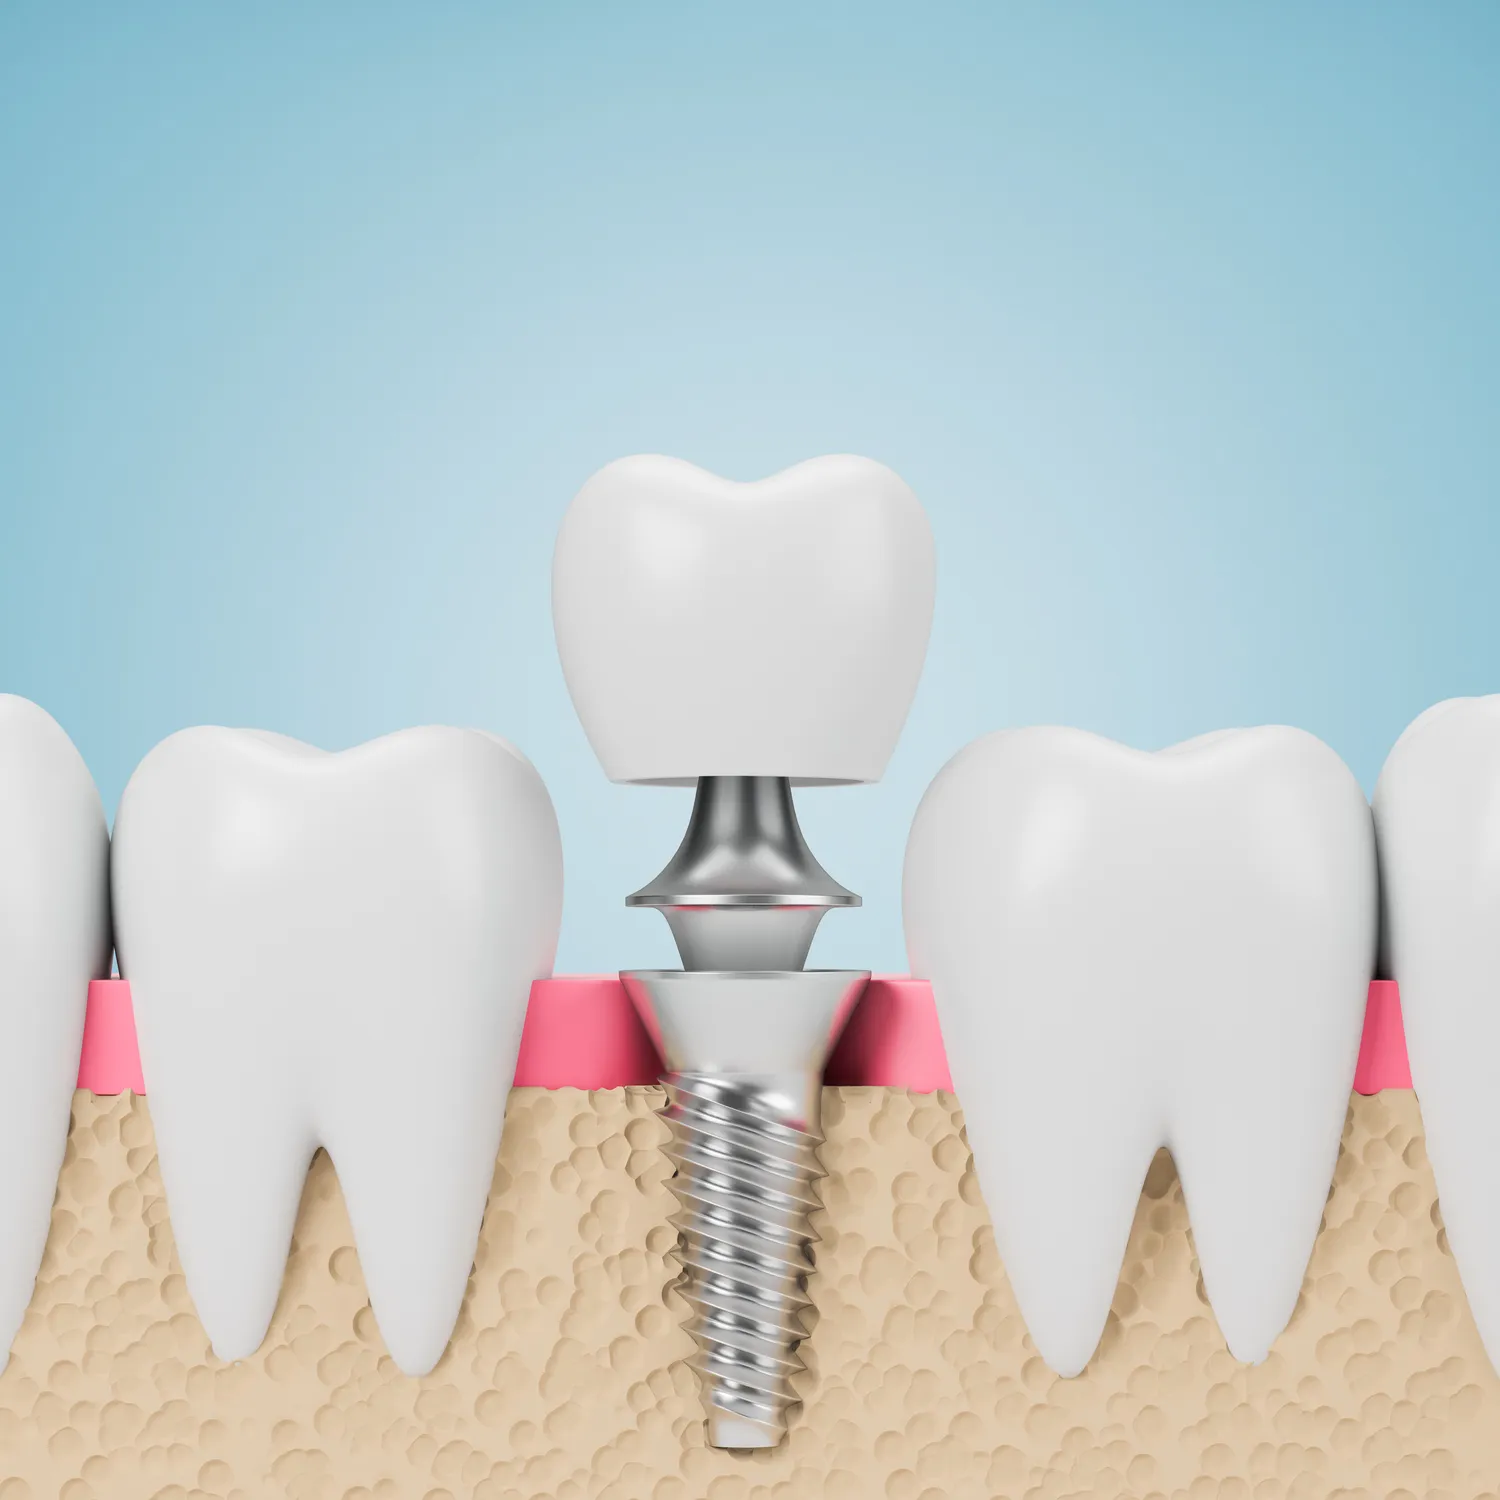

Proces zakupu implantów zębowych w Lublinie zazwyczaj rozpoczyna się od konsultacji ze stomatologiem, który oceni stan zdrowia jamy ustnej pacjenta oraz zaproponuje odpowiedni plan leczenia. Podczas pierwszej wizyty lekarz przeprowadzi szczegółowy wywiad medyczny oraz wykona zdjęcia rentgenowskie lub tomografię komputerową, aby dokładnie ocenić warunki anatomiczne do wszczepienia implantu. Następnie pacjent otrzymuje informacje dotyczące kosztów oraz czasu trwania leczenia. Po zaakceptowaniu planu leczenia następuje etap chirurgiczny, podczas którego implant jest wszczepiany w kość szczęki lub żuchwy. Po kilku miesiącach następuje etap odbudowy protetycznej, kiedy to na implancie mocowane są korony zębowe. Cały proces może potrwać od kilku miesięcy do nawet roku, w zależności od indywidualnych potrzeb pacjenta oraz ewentualnych dodatkowych zabiegów wymaganych przed wszczepieniem implantu.

Implanty zębowe oferują wiele korzyści dla pacjentów w Lublinie, które sprawiają, że są one coraz bardziej popularnym rozwiązaniem w stomatologii. Przede wszystkim, implanty pozwalają na przywrócenie pełnej funkcjonalności jamy ustnej, co oznacza możliwość swobodnego jedzenia i mówienia bez obaw o wypadanie protez. Dodatkowo, implanty wyglądają i czują się jak naturalne zęby, co znacząco wpływa na estetykę uśmiechu pacjenta. Kolejną zaletą jest ich trwałość – odpowiednio pielęgnowane implanty mogą służyć przez wiele lat, a nawet całe życie. W przeciwieństwie do tradycyjnych protez, które mogą wymagać częstej wymiany lub regulacji, implanty nie zmieniają swojego kształtu ani pozycji. Ponadto, wszczepienie implantu wspiera zdrowie kości szczęki poprzez stymulację kości podczas żucia, co zapobiega jej zanikowi. Warto również zauważyć, że implanty nie wpływają negatywnie na sąsiednie zęby, co jest częstym problemem przy innych metodach uzupełniania braków zębowych.

Czas gojenia po wszczepieniu implantów zębowych może się różnić w zależności od indywidualnych uwarunkowań pacjenta oraz specyfiki danego przypadku klinicznego. Zazwyczaj proces ten trwa od kilku tygodni do kilku miesięcy. W pierwszym etapie następuje integracja implantu z kością szczęki lub żuchwy – to kluczowy moment dla sukcesu całego leczenia. W tym czasie ważne jest przestrzeganie zaleceń lekarza dotyczących diety oraz higieny jamy ustnej, aby zapewnić optymalne warunki do gojenia się tkanek. Po około trzech do sześciu miesięcy lekarz oceni stan implantu i zdecyduje o dalszych krokach – jeśli wszystko przebiega prawidłowo, można przystąpić do etapu odbudowy protetycznej polegającej na mocowaniu koron na wcześniej wszczepionych implantach. Warto pamiętać, że każdy organizm reaguje inaczej i czas gojenia może być wydłużony u osób z problemami zdrowotnymi czy osłabionym układem odpornościowym.